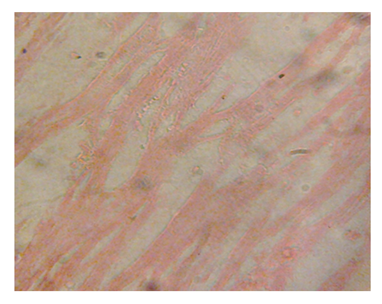

Figure 1 Liver micrograph of control rat showing at 3 and 5 weeks. (H & E stain X400).

Figure 1 Liver micrograph of diabetic rat showing mild periportal lymphocytic infiltration(P) and hepatocyte disorientation (H) at 3 weeks.(H & E stain X400).